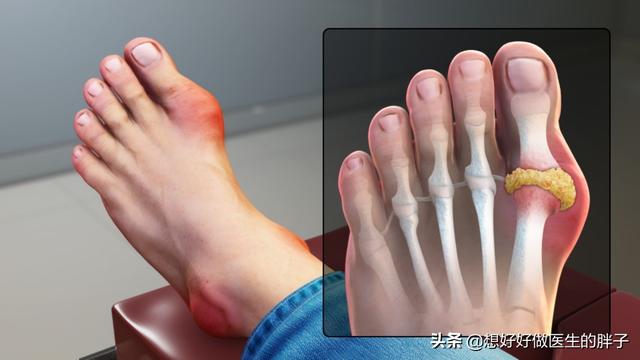

Comme cela a déjà été dit.La goutte provoque des rougeurs, des gonflements, de la chaleur et des douleurs très typiques chez le patient.Lors de la première crise, la goutte a tendance à se situer plus souvent dans la région des orteils, mais ce n'est pas absolu, la goutte qui se manifeste dans les coudes, les genoux, les doigts, ainsi que les poignets est de plus en plus fréquente.

La détermination de la goutte dépend principalement des articulations. Au début de l'apparition de la goutte, 53 % à 70 % des patients ont les articulations du premier orteil (appelées goutte du pied) rouges, gonflées, chaudes et douloureuses, généralement multiples, certaines pouvant aussi se manifester sous forme d'articulations multiples. Elle est fixe et asymétrique, et peut progressivement envahir des articulations plus importantes telles que les chevilles, les genoux, les poignets et les coudes.

Le premier symptôme est souvent une douleur articulaire qui se manifeste principalement au niveau des pieds, en particulier du gros orteil.

Pourquoi notre gros orteil ? Le raisonnement est simple : vous pouvez essayer d'obtenir vos propres liens corporels.Vous constaterez que cette zone d'articulation est une zone à température relativement basse.Si vous avez appris la physique ou si vous connaissez la solubilité, vous savez que plus la température est élevée, plus la solubilité est grande, et qu'au contraire, plus la température est basse, plus la solubilité est faible ! Tout comme nous dissolvons habituellement du sucre et de l'eau salée, est-il plus facile de dissoudre du sucre et du sel dans de l'eau à température élevée ? Et la température plus basse n'est pas plus difficile à dissoudre, mais plus susceptible de se déposer ?L'articulation du gros orteil est un peu dans ce cas, la température basse est alors plus propice à la formation de nos cristaux d'urate, entraînant des lésions tissulaires et provoquant des douleurs inflammatoires !

En outre, cetteL'articulation du gros orteil est également l'articulation la plus vulnérable aux traumatismes.L'acide urique peut se déposer dans les articulations à la suite d'un accident ou d'un traumatisme mineur, ce qui favorise le dépôt de cristaux d'acide urique.Bien entendu, la douleur articulaire provoquée par la goutte n'est pas limitée à cet endroit, comme le dos du pied, la cheville, le genou, etc. sont des parties communes, et il n'y a généralement pas de symétrie, et la douleur localisée en touchant le pied présente une rougeur, un gonflement et une chaleur, en plus de la chaleur de la peau au toucher.

Les orteils, la zone où les urates ont tendance à s'accumuler, et lorsque la goutte frappe, la douleur, littéralement, est atroce.

Lors d'une crise aiguë de goutte, on observe souvent une rougeur, un gonflement, une chaleur, une douleur et un dysfonctionnement localisés importants dans les articulations touchées (le plus souvent le gros orteil et le dos du pied).